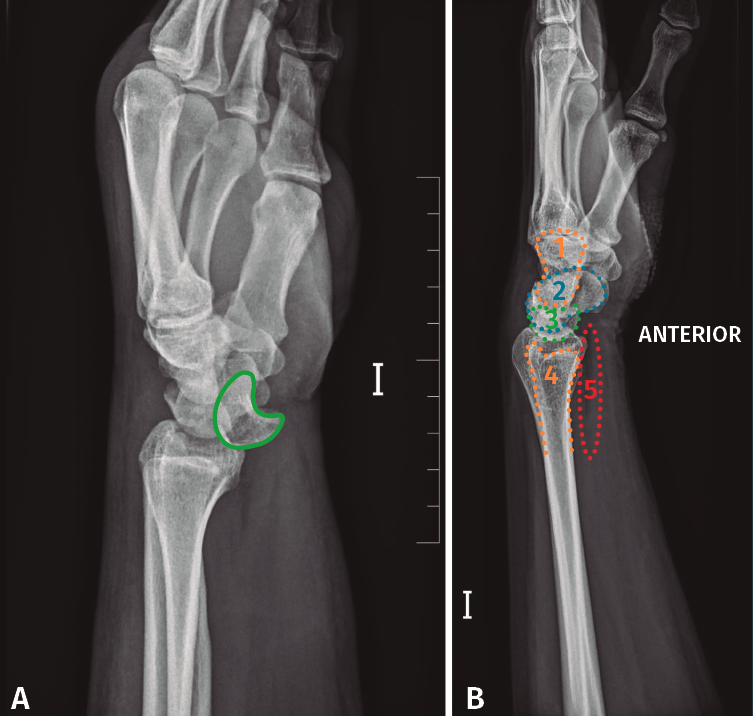

Se solicitó una radiografía anteroposterior y lateral pura de muñeca izquierda, en la que se observa una luxación transestiloperilunar (Figura 2).

Figura 2. A: radiografía anteroposterior en la que se observa la disrupción de los arcos de Gilula. Semilunar en flexión volar (rojo); B: radiografía lateral pura de muñeca en la que se observa la pérdida de la congruencia semilunar, hueso grande y 3.er metatarsiano (verde).